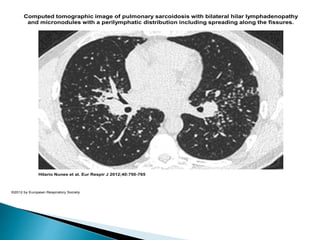

 Micronodules in a subpleural and bronchovascular

distribution.

 Fissural nodularity and bronchial distortion.

 Irregular linear opacities, ground-glass shadowing

related to bronchovascular bundles, and nodular or ill-

defined shadows.

 Air trapping due to small airway granulomata

common.

 Endobronchial disease in 55%.

 Minority has UIP pattern, associated with worse

prognosis.

 Hilar and mediastinal lymphadenopathy.

Computed tomographic image of pulmonary sarcoidosis with bilateral hilar lymphadenopathy

and micronodules with a perilymphatic distribution including spreading along the fissures.

Hilario Nunes et al. Eur Respir J 2012;40:750-765

©2012 by European Respiratory Society